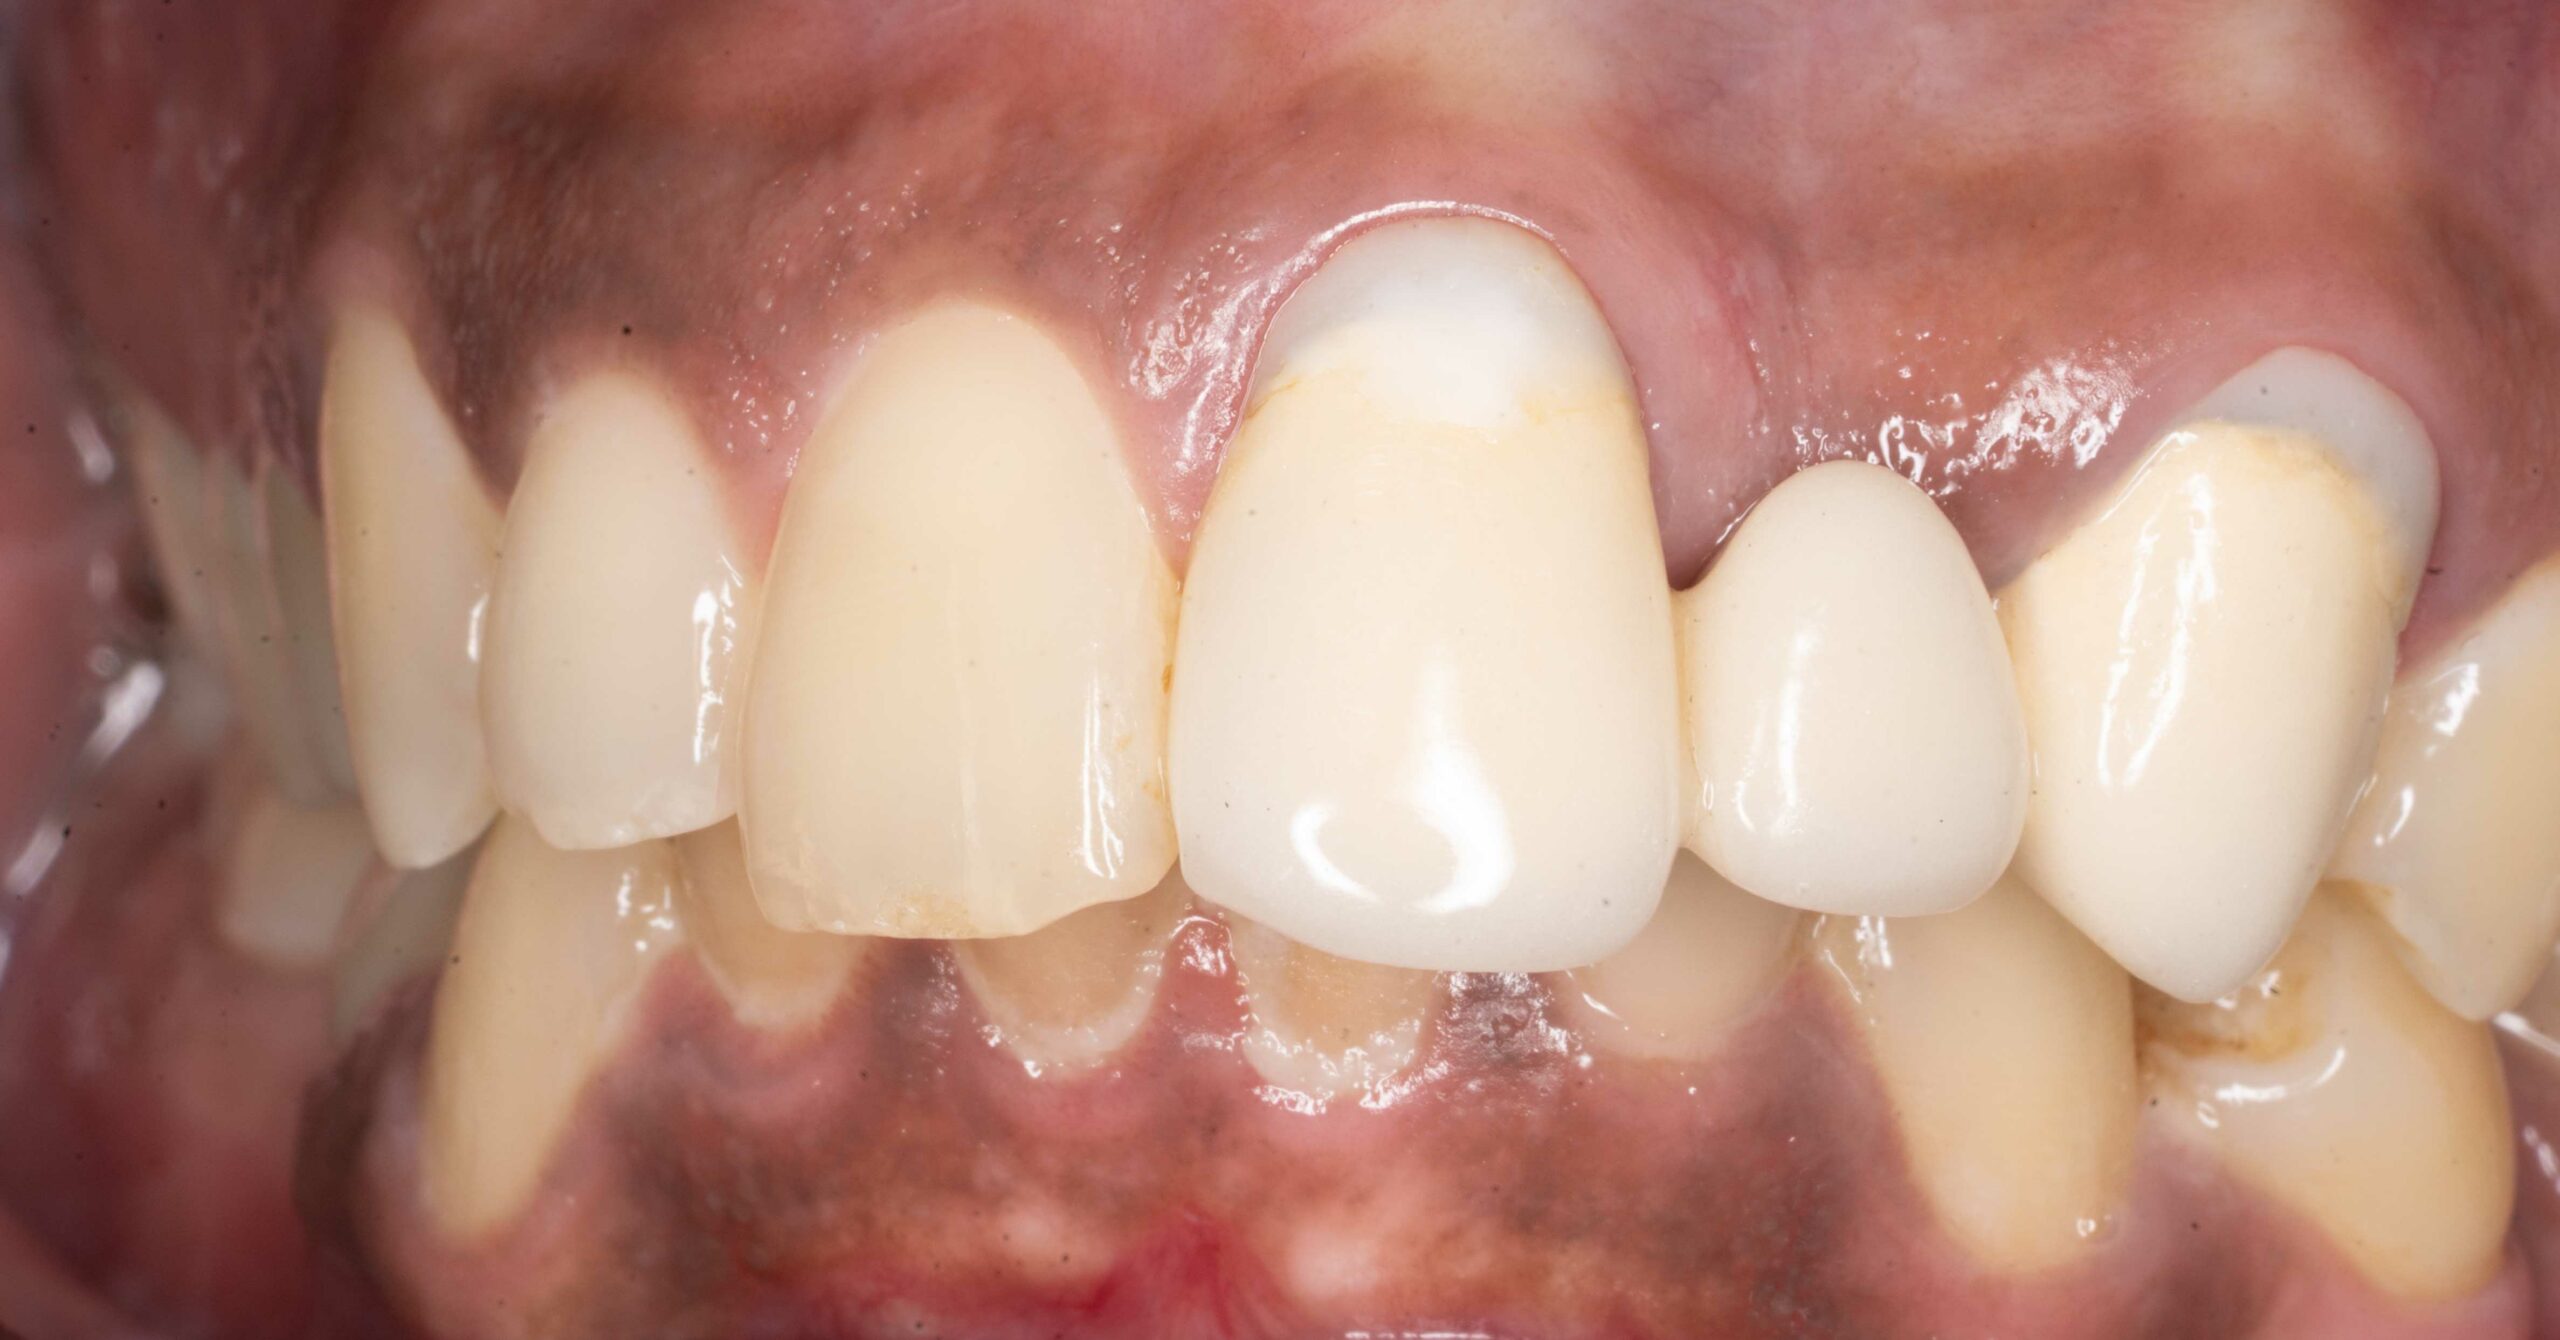

Wymiana mostu

Pacjent zgłosił się w celu wymiany mostu na zębach 21 23 odtwarzającego brak zęba 22.

Leczenie obejmowało:

- usunięcie poprzedniej odbudowy

chirurgiczną plastykę dziąsła

- wykonanie nowego ceramicznego mostu

Leczenie przeprowadził lek. dent. Kamil Kikowicz